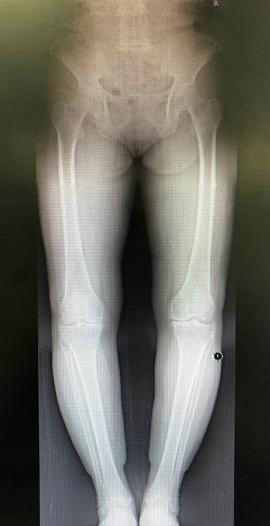

影像学检查有助于明确膝关节骨性关节炎的进展程度。X线平片检查早期可无明显异常,逐渐出现关节间隙狭窄,表明关节软骨开始变薄。开始时关节间隙在不负重时正常,承重后出现狭窄。病变后期,关节间隙有显著狭窄,而后出现骨质硬化,最后关节边缘变尖,有骨赘形成。CT及MRI检查可早期发现关节软骨及软骨下骨质的异常改变。

值得一提的是,并不是所有人的影像学检查结果都与临床症状完全符合,由于患者的耐受程度不同,有一些影像学检查表现很轻微的患者,临床症状也可能很重,而对于运动强度较大的特殊人群,如专业运动员等,即使影像学检查显示关节退变严重,也可以没有明显临床症状。